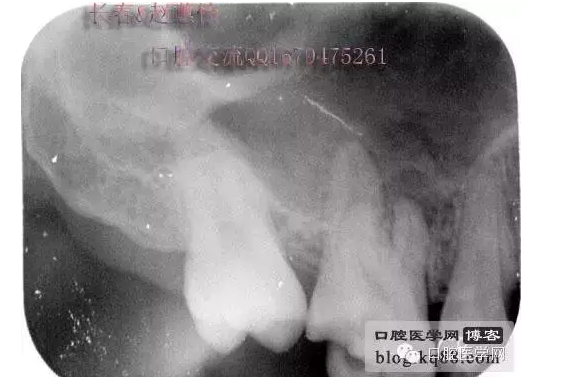

這個(gè)是術(shù)前照片,一切如常

患牙是死髓牙,患者是一位大學(xué)生,探查根管時(shí)一切都很順利,就有點(diǎn)忽視了,當(dāng)然這個(gè)臺(tái)階是人為造成的,造成的原因呢就是使用機(jī)擴(kuò)時(shí)跳號(hào)了,所以大家一定要逐號(hào)使用啊,預(yù)備出一個(gè)臺(tái)階,后續(xù)要搭上很長(zhǎng)時(shí)間才能搞定,好不容易越過臺(tái)階下去的銼,一提拉出來就下不去了,著實(shí)讓人郁悶,一切都要從頭再來,這個(gè)時(shí)候再下銼的時(shí)候就必須預(yù)彎了。而且要多角度試探,很是考驗(yàn)?zāi)托牡臅r(shí)候。吃一塹長(zhǎng)一智嘛!